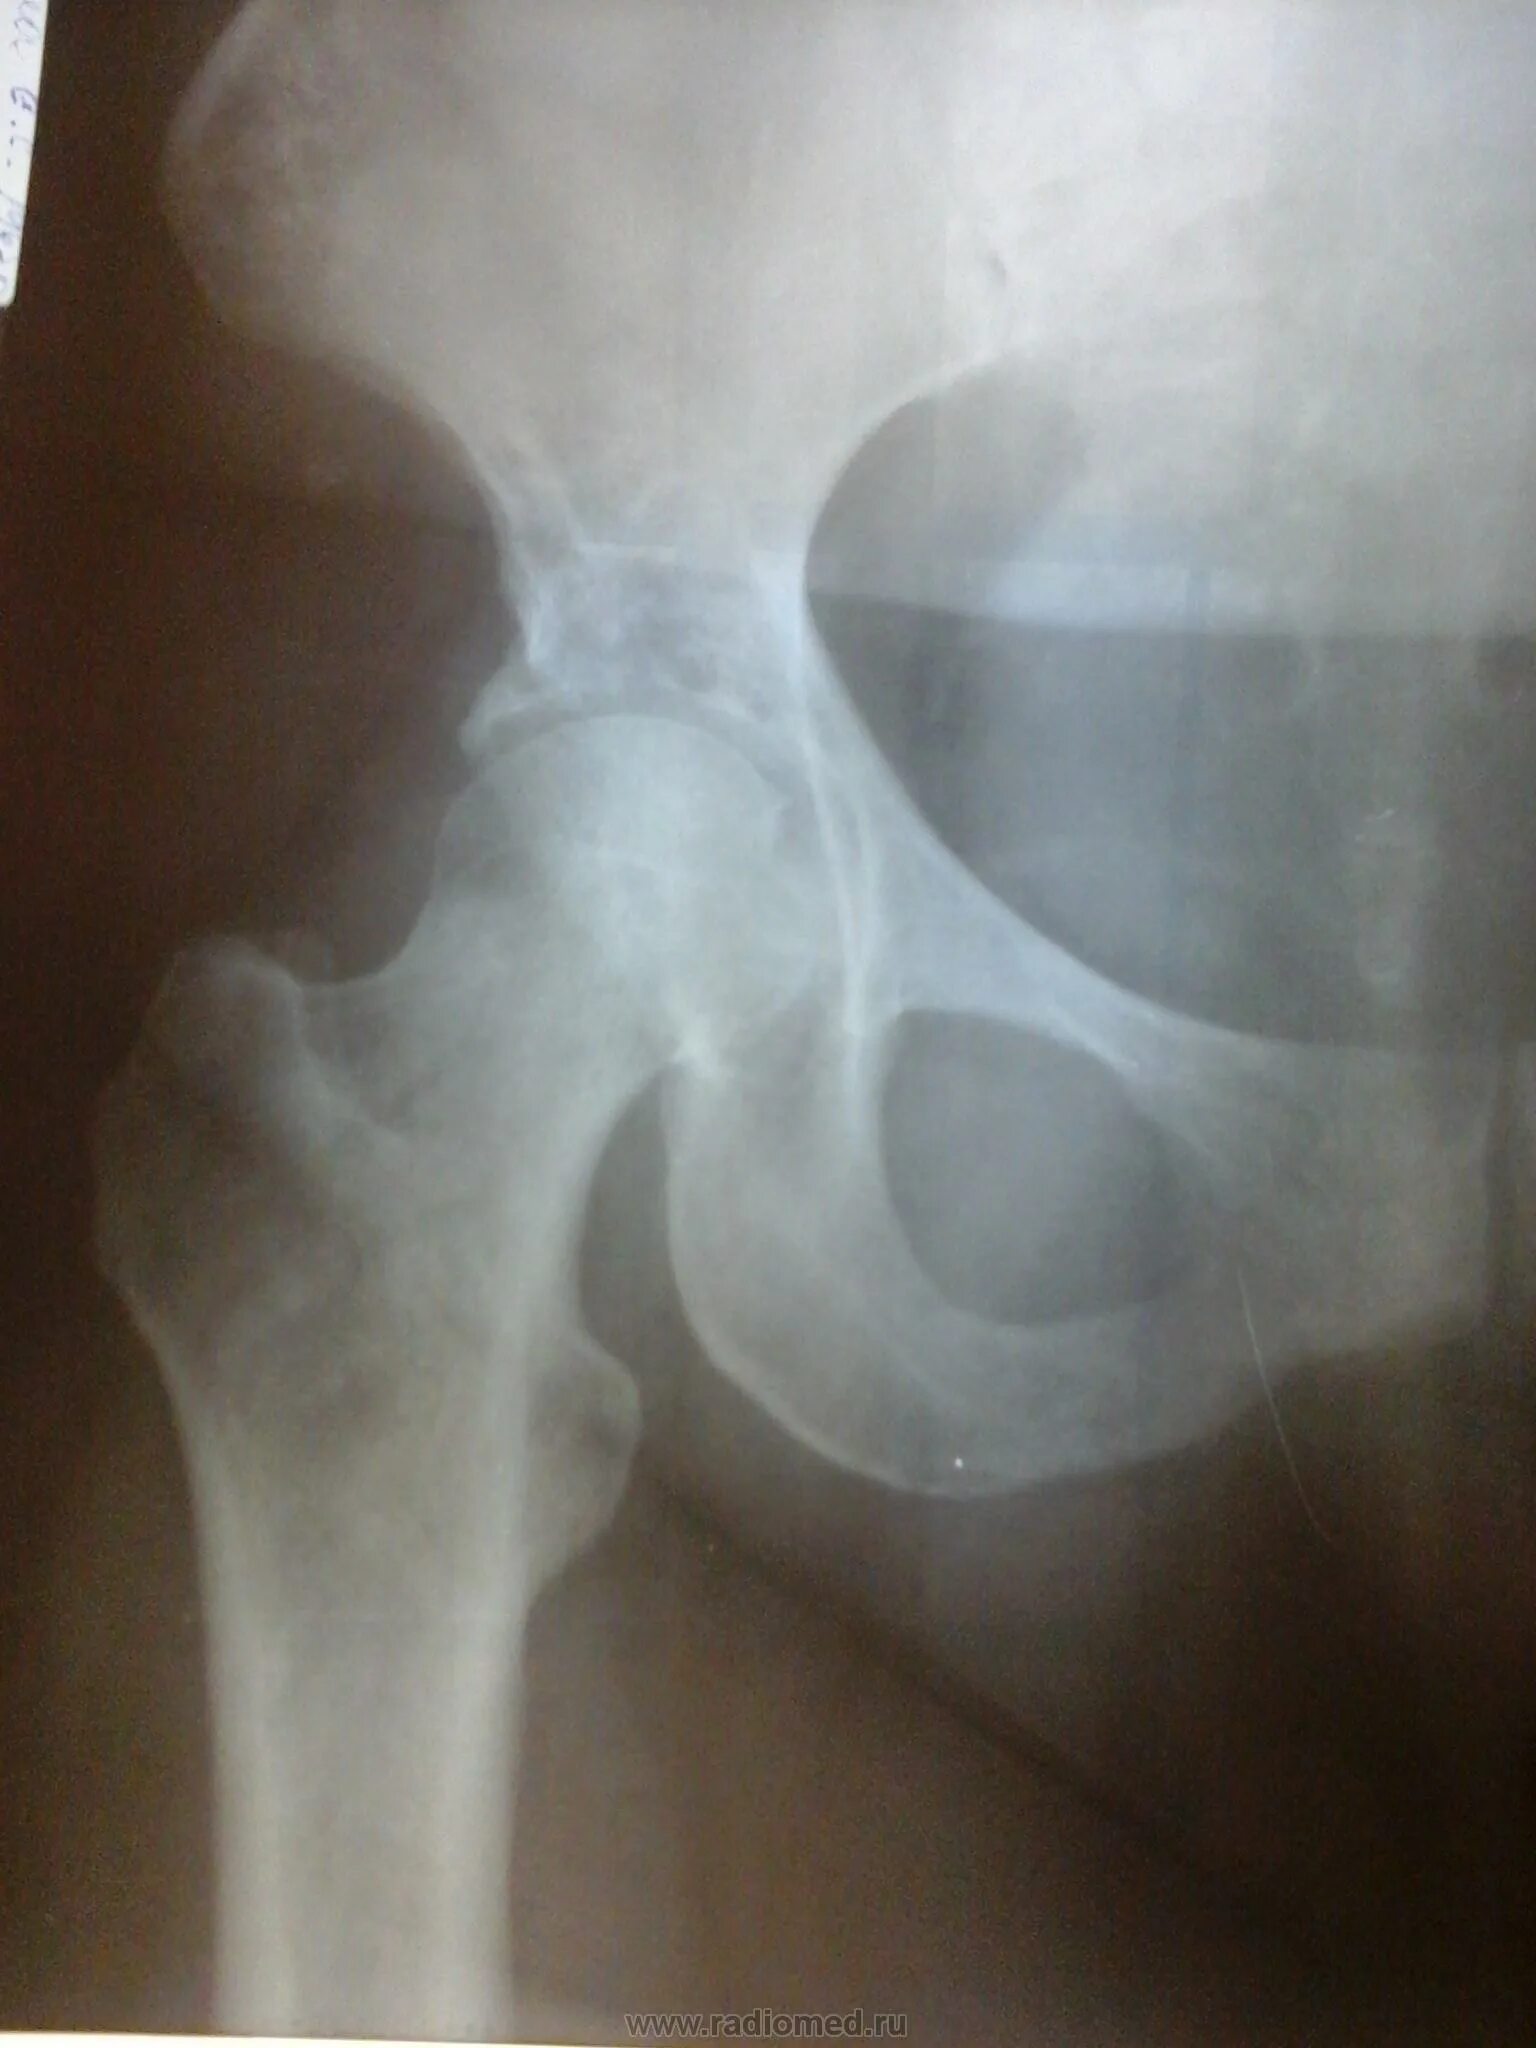

Склероз вертлужной впадины